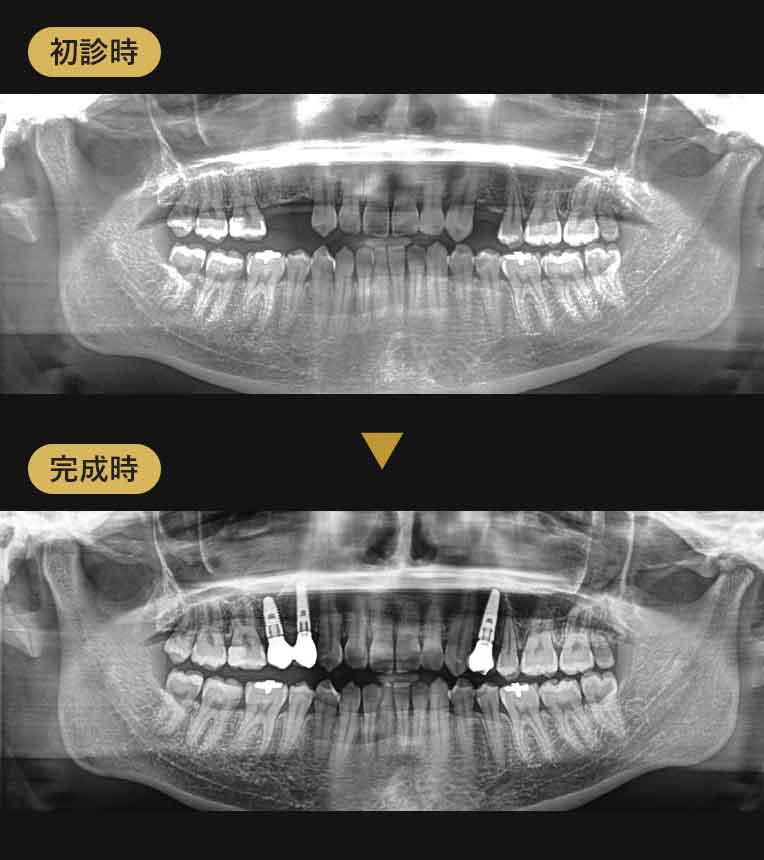

- 21歳 左上4番 右上4、5番が先天性欠如

- インプラント3本 1,408,000円

- 4ヶ月

審美性にも非常に優れた埋入

上部構造はジルコニア